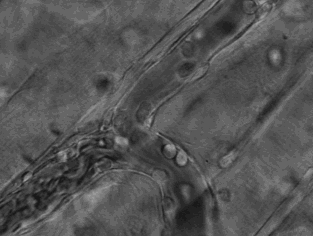

下圖像「卜」字形水管的物體是顯微鏡底下的血管,血管下端流動很快速的顆粒是血液,而上方緩慢移動的透明白色小球則是免疫細胞,這是免疫細胞偵測到身體發生炎症和創傷組織的地方,穿過血管壁奔赴戰場的顯微攝影。

當免疫細胞作戰後或衰老時會死亡,然後慢慢地釋放細胞內的物質

下圖中即顯示,透明圓形狀物體即為免疫細胞,正在慢慢地瓦解,並釋放出細胞內的物質。